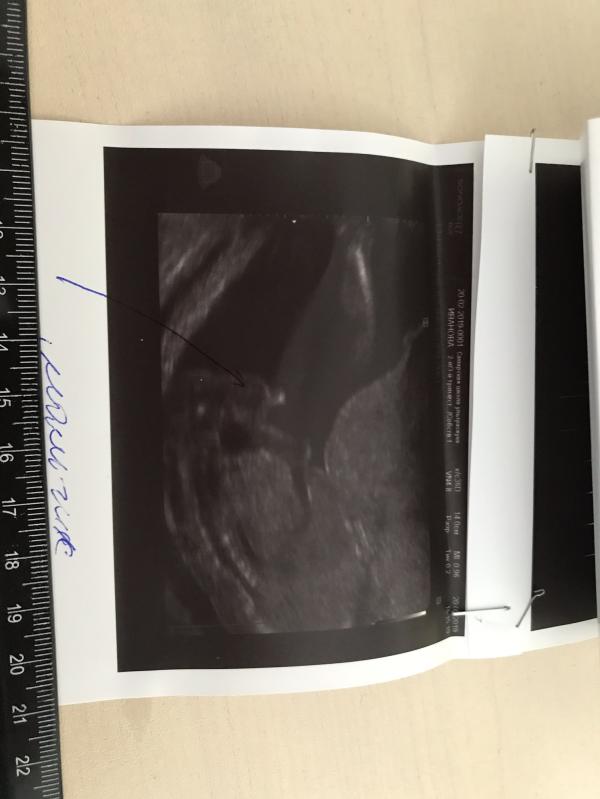

В 18 недель делала второе УЗИ в Самарской школе Ультразвука и нам сказали, что будет мальчик👶 Показали нам писюн, но я слабо что-то там увидала, если честно. Захотела сейчас начать покупать вещички для малыша, а муж тут взял и выдал мне вчера: - а вдруг девочка будет, а купим все для мальчика?! Иногда же врачи тоже ошибаются )

И сегодня я весь день думаю и рассматриваю фото нашего УЗИ и так как не видала как выглядит девочка не могу понять 🤦🏻♀️🤯🙄 Вот наше УЗИ, подскажите кто что знает, может у кого-то так и было))))🙏🙏🙏

Но на фото у Вас прям мальчик)))

Вот и хочу такие мнения услышать, кто понимает что видно на фото)))